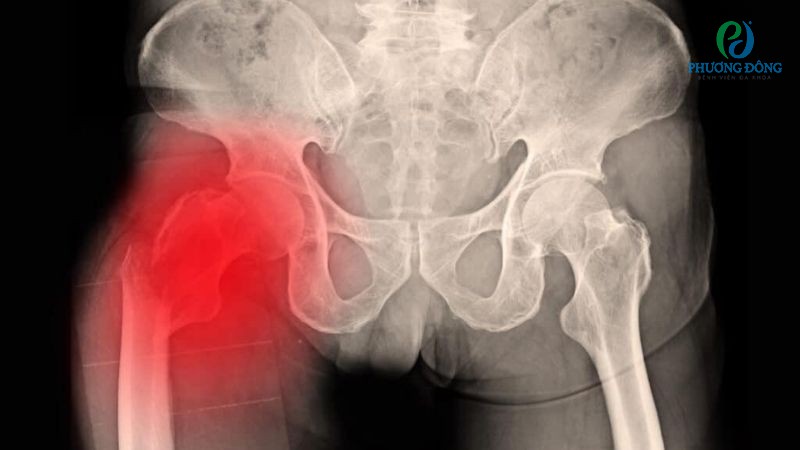

Sau chấn thương ngoại lực, xương chậu phụ nữ có nguy cơ cao bị di lệch. Tuy nhiên điều này không ảnh hưởng đến khả năng mang thai, hay thai làm tổ trong tử cung người mẹ.

Gãy xương chậu không ảnh hưởng đến khả năng mang thai của người mẹ

Chưa dừng ở đó, có con khi xương chậu chưa lành hoàn toàn còn ảnh hưởng đến quá trình sinh nở, đặc biệt qua đường âm đạo. Đường ra của trẻ khi này bị hạn chế, bác sĩ thường khuyến nghị phẫu thuật mổ lấy thai hơn con đường tự nhiên.

Nhìn chung, khả năng mang thai của phụ nữ không liên quan đến hình thái xương chậu. Song những biến chứng hậu chấn thương sẽ ảnh hưởng trực tiếp đến khả năng sinh thường.